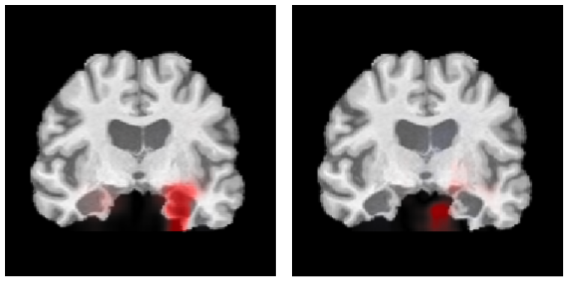

For comparison, figure 4 shows both the ST and OT explanations for another sample true positive image, shown in coronal slices. The ST correctly highlighted the region of the hippocampus, with more emphasis given to the left side. On the other hand, the OT identified a region outside of the brain as being relevant.

Refer to caption

Figure 4: Visual assessment (best viewed in color): ST explanation (left) and OT explanation (right) for a sample true positive image shown in coronal slices. While the ST correctly highlighted the hippocampus, the OT highlighted a region outside the brain.